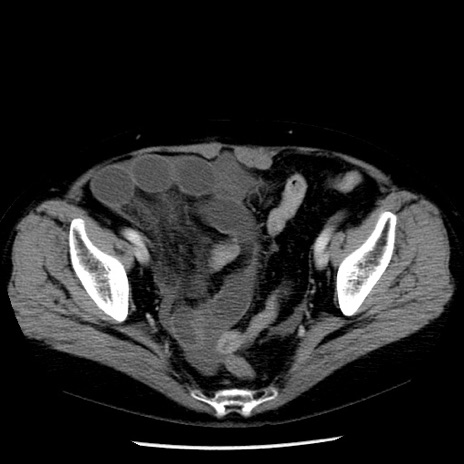

症例13(横断像)

【症例】70歳代女性

【主訴】腹痛、嘔吐

【現病歴】15時間程前(昨晩)より腹痛あり。今朝になっても症状の改善なく、嘔吐あり。腹痛も増悪あり、救急外来受診。

【既往歴】子宮癌全摘術後

【身体所見】意識清明、BP 121/72mmHg、P 74bpm、SpO2 100%(RA)、腹部:平坦・軟、腸雑音ほぼ聴取せず。下腹部・心窩部・臍左上に圧痛あり。反跳痛なし。

【データ】WBC 10600、CRP 0.15